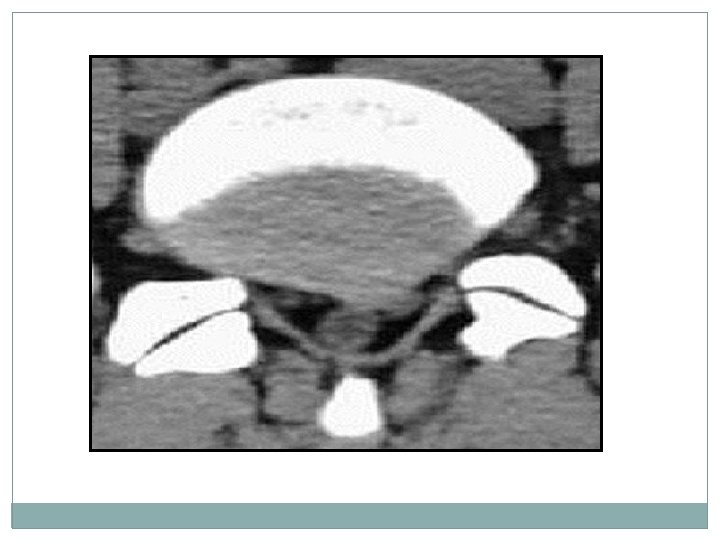

imagerie � 2 La tomodensitométrie (TDM) du rachis lombo sacré: permet de préciser l’HERNIE DISCALE son siège, de son volume, sa migration, son environnement osseux.